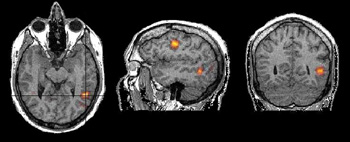

Las vistas ortogonales hacen referencia a un conjunto de imágenes mutuamente perpendiculares. Esto localiza una región determinada de activación en los tres ejes que definen la forma volumétrica del cerebro.

Voluntario adulto que genera verbos. En la vista axial, la ubicación exacta de la activación en el lóbulo temporal es difícil de determinar. Las líneas negras en la vista axial corresponden a la ubicación de las vistas sagital y coronal. Estas tres vistas nos permiten determinar la ubicación de la activación en la circunvolución temporal media.

Paciente adulto de sexo masculino diestro con convulsiones intratables provenientes del polo temporal izquierdo y que realiza una tarea de lenguaje que consiste en escuchar una historia. No se detectaron lesiones estructurales en esta región. Está programada una resección temporal izquierda. Las vistas ortogonales permiten evaluar la extensión de las áreas del lenguaje y la distancia entre su borde anterior y el polo temporal (línea de color anaranjado). El neurocirujano puede usar estos hallazgos como guía para adaptar la resección temporal.